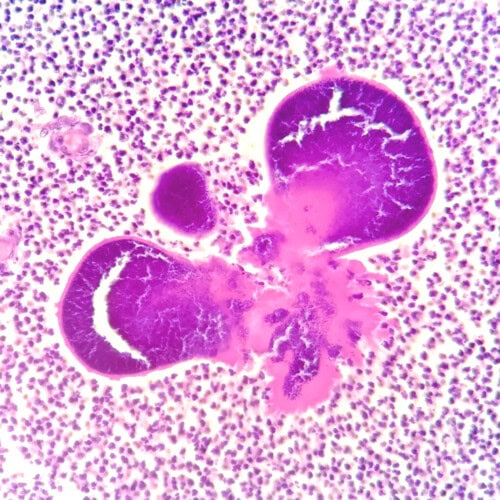

Les biopsies cutanées (LAPVSO) montrent un tissu de granulation dans lequel aucune structure épithéliale n’est visible. Ce tissu est infiltré de nombreux granulocytes neutrophiles plus ou moins altérés associés à une population inconstante de lymphocytes, plasmocytes et histiocytes. Au sein de cette lésion on observe plusieurs colonies bactériennes géantes constituée de coques et entourées d’un matériel éosinophile hyalin (phénomène de Splendore-Hoëppli).

Photos 6 et 7 : Examen histopathologique montrant principalement des granulocytes neutrophiles entourant des colonies bactériennes enveloppées dans un matériel éosinophile hyalin (JC Husson, LAPVSO, HE)

Histopathologiquement, l’une des caractéristiques de la botryomycose, outre la présence d’une cellulite pyogranulomateuse, est la mise en évidence du phénomène de Splendore-Hoeppli, correspondant à la visualisation, autour des colonies bactériennes Gram positives, de dépôts éosinophiles rayonnants ou annulaires (possible aussi avec des champignons ou des parasites).